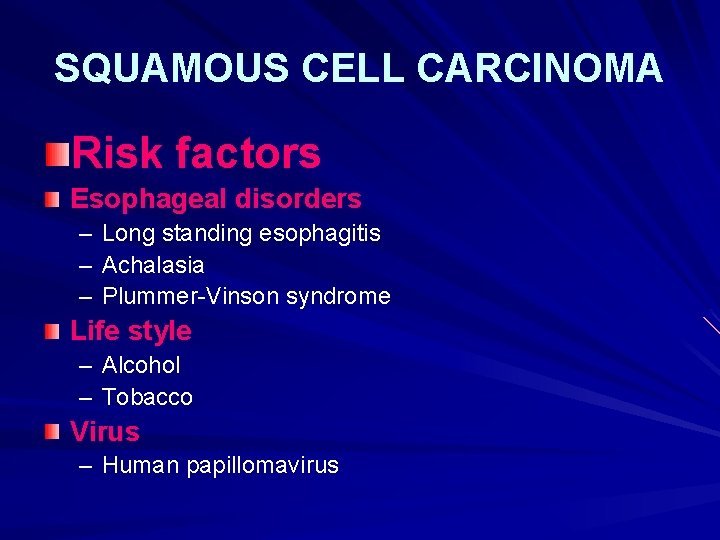

SQUAMOUS CELL CARCINOMA Risk factors Esophageal disorders – Long standing esophagitis – Achalasia – Plummer-Vinson syndrome Life style – Alcohol – Tobacco Virus – Human papillomavirus